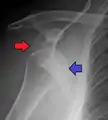

Anterior dislocation of the right shoulder. AP X ray

A Hill–Sachs lesion is an impaction of the head of the humerus left by the glenoid rim during dislocation.[6] Hill-Sachs deformities occur in 35–40% of anterior dislocations. They can be seen on a front-facing X-ray when the arm is in internal rotation.[9] Bankart lesions are disruptions of the glenoid labrum with or without an avulsion of bone fragment.

Damage to the axillary artery[10] and axillary nerve (C5, C6) may result. The axillary nerve is injured in 37% making it the most commonly injured structure with this type of injury.[11] Other common, associated, nerve injuries include injury to the suprascapular nerve (29%) and the radial nerve (22%).[11] Axillary nerve damage results in a weakened or paralyzed deltoid muscle and as the deltoid atrophies unilaterally, the normal rounded contour of the shoulder is lost. A person with injury to the axillary nerve will have difficulty in abducting the arm from approximately 15° away from the body. The supraspinatus muscle initiates abduction from a fully adducted position.